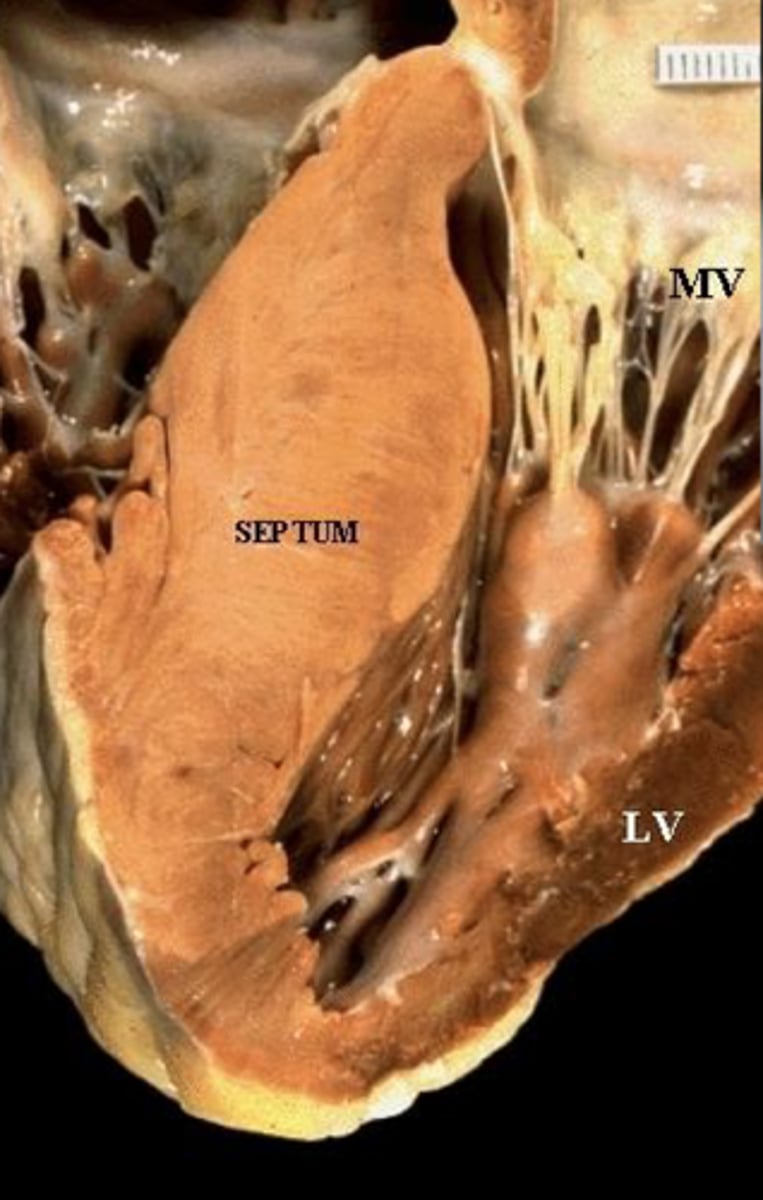

Myopathy (infantile hypertrophic cardiomyopathy), exercise intolerance

AR Pompe disease II (lysosomal alpha-1,4-glucosidase deficiency)

Can't breakdown lysosomes to release glycogen in liver or muscle (PAS+)

Sudden death in young athletes

Differential: Myocete disarray (B-myosin heavy chain or myosin-binding protein C mutation)

Tx: replace enzyme